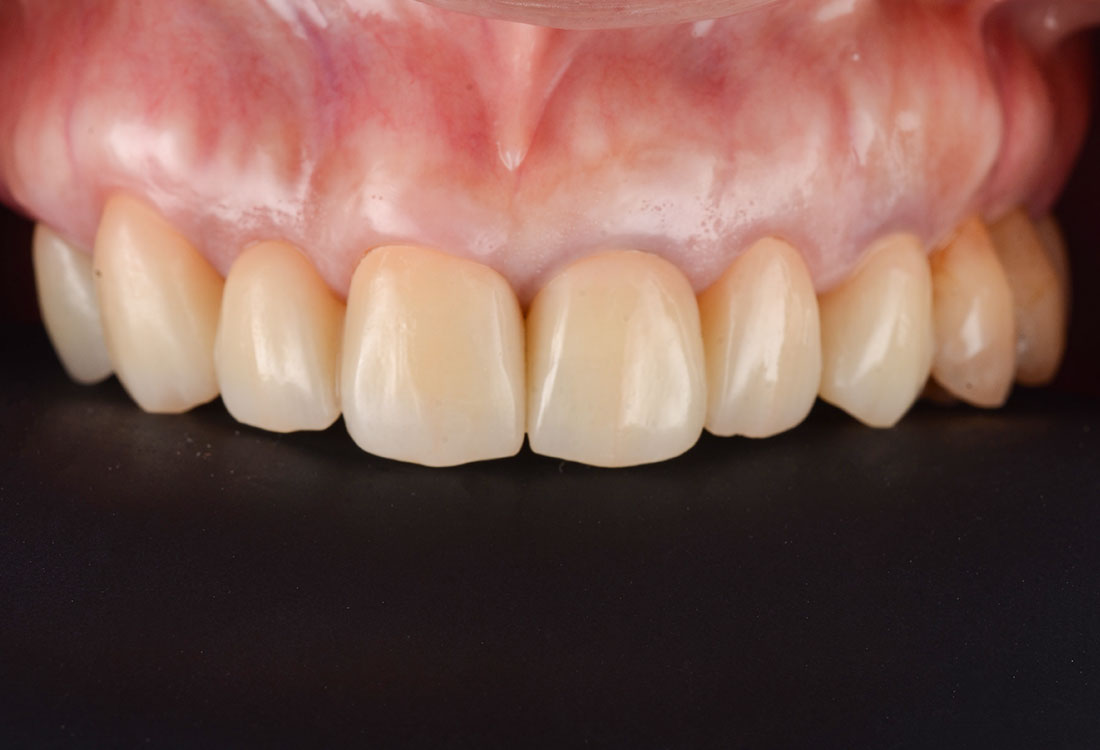

今回は着色したジルコニアを選択しました。

着色した被せ物を使うことでとても自然な仕上がりになりました。